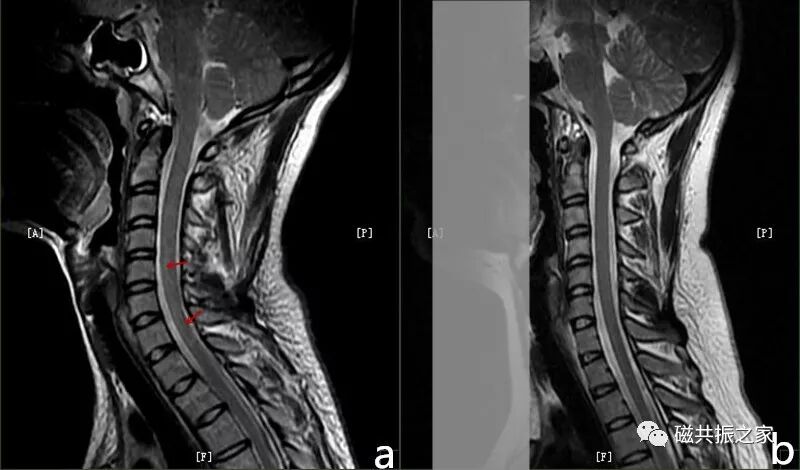

运动伪影由心脏和患者运动引起,像颈部吞咽动作引起的伪影可能被误认为脊髓病变,添加颈前饱和带可抑制。